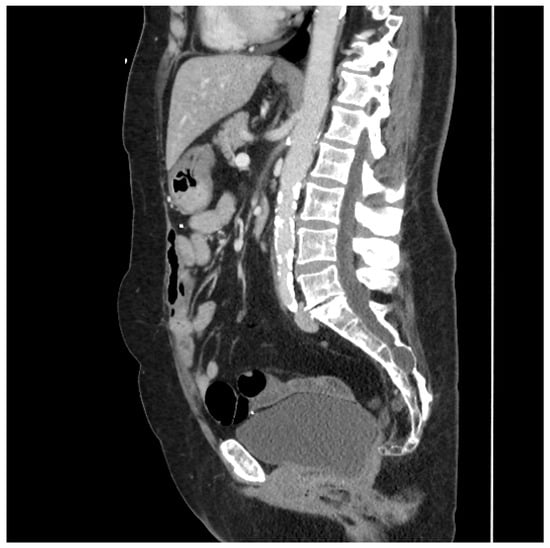

This type of flap was used in two patients. The first underwent total proctocolectomy for fistulizing perianal disease and a rectovaginal fistula. She had a diminutive greater omentum found during surgery that was deemed unsuitable for an omental pedicle flap. Close colonic and rectal dissection were carried out, which left a sufficient amount of sigmoid mesocolon in situ. The sigmoid mesocolon was advanced inferiorly and sutured to the pelvic brim to close it off and prevent the small bowel from entering the pelvis. The blood supply of the mesocolon was preserved as the inferior mesenteric artery was not ligated, and the superior rectal artery was left intact. A 15 Fr drain was left in the pelvis at the end of the operation. A CT scan performed four years after surgery demonstrated the resilience of this flap and its prolonged ability to prevent the small bowel from adhering to the proctectomy resection bed (See Figure 2).

Figure 2.

Sagittal CT scan performed four years after proctocolectomy and sigmoid mesocolic flap. The mesocolic flap is seen here filling the pelvis and adherent to the back of the bladder, forming a sling-like configuration, thus preventing the small bowel from adhering to the proctectomy resection bed in the pelvis. (Used with permission from the Mayo Foundation for Medical Education and Research; all rights reserved).